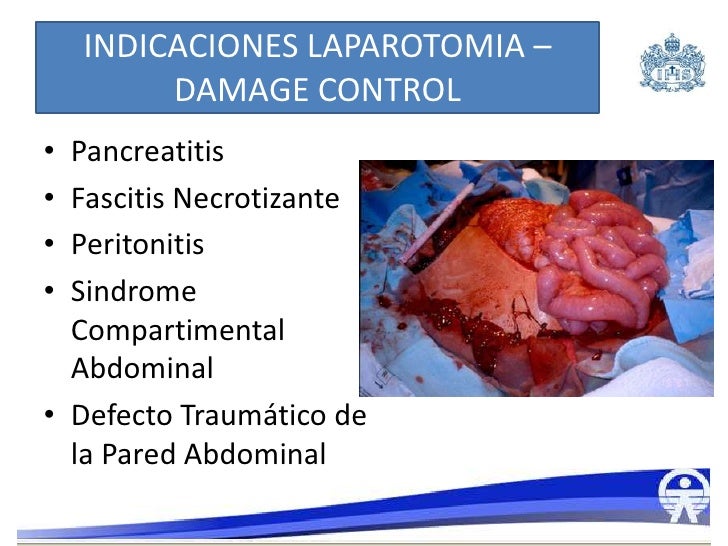

Sepsis intra abdominal

Source: es.slideshare.net

Sepsis intra abdominal

Source: es.slideshare.net

Sepsis intra abdominal

Source: es.slideshare.net